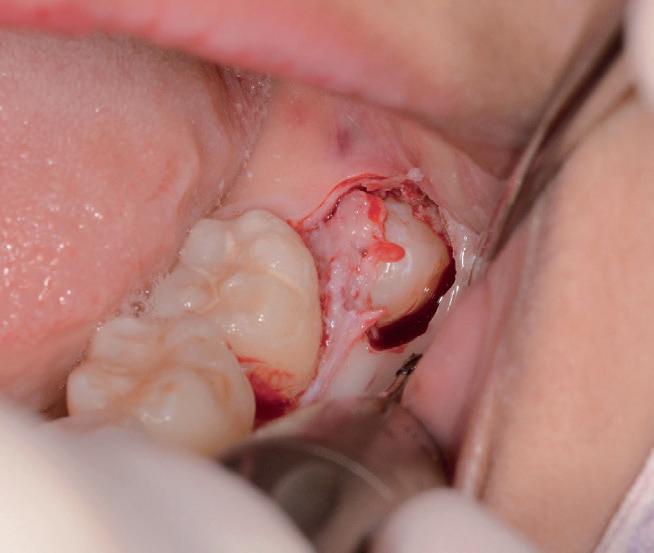

Abbiamo estratto il dente del giudizio inferiore di destra in una paziente di 22 anni, un’amica, utilizzando il manipolo dritto, con il proposito di fare delle foto dell’intervento. Figg. 173-179

Dalla radiografia (Fig. 166) sembrava che il dente avesse due radici separate, quindi è stato eseguito un taglio orizzontale utilizzando il manipolo dritto per sezionare il dente a metà. Tuttavia, la corona si è frat-

turata poiché in realtà le radici erano unite e il dente non è stato sezionato completamente.

Bisogna prendere in considerazione sempre molti fattori come, ad esempio, la forma delle radici, il sottosquadro nella regione distale del secondo molare e l’osso alveolare disto-vestibolare. Se necessario la corona e le radici vengono separate intenzionalmente per estrarre il dente, proprio come in questo caso.

Figg. 173-179 - Caso 3: tecnica di estrazione con divisione orizzontale utilizzando il manipolo dritto. Fig. 173 Fig. 174 Fig. 175 Fig. 176 Fig. 177 Fig. 178 Fig. 179